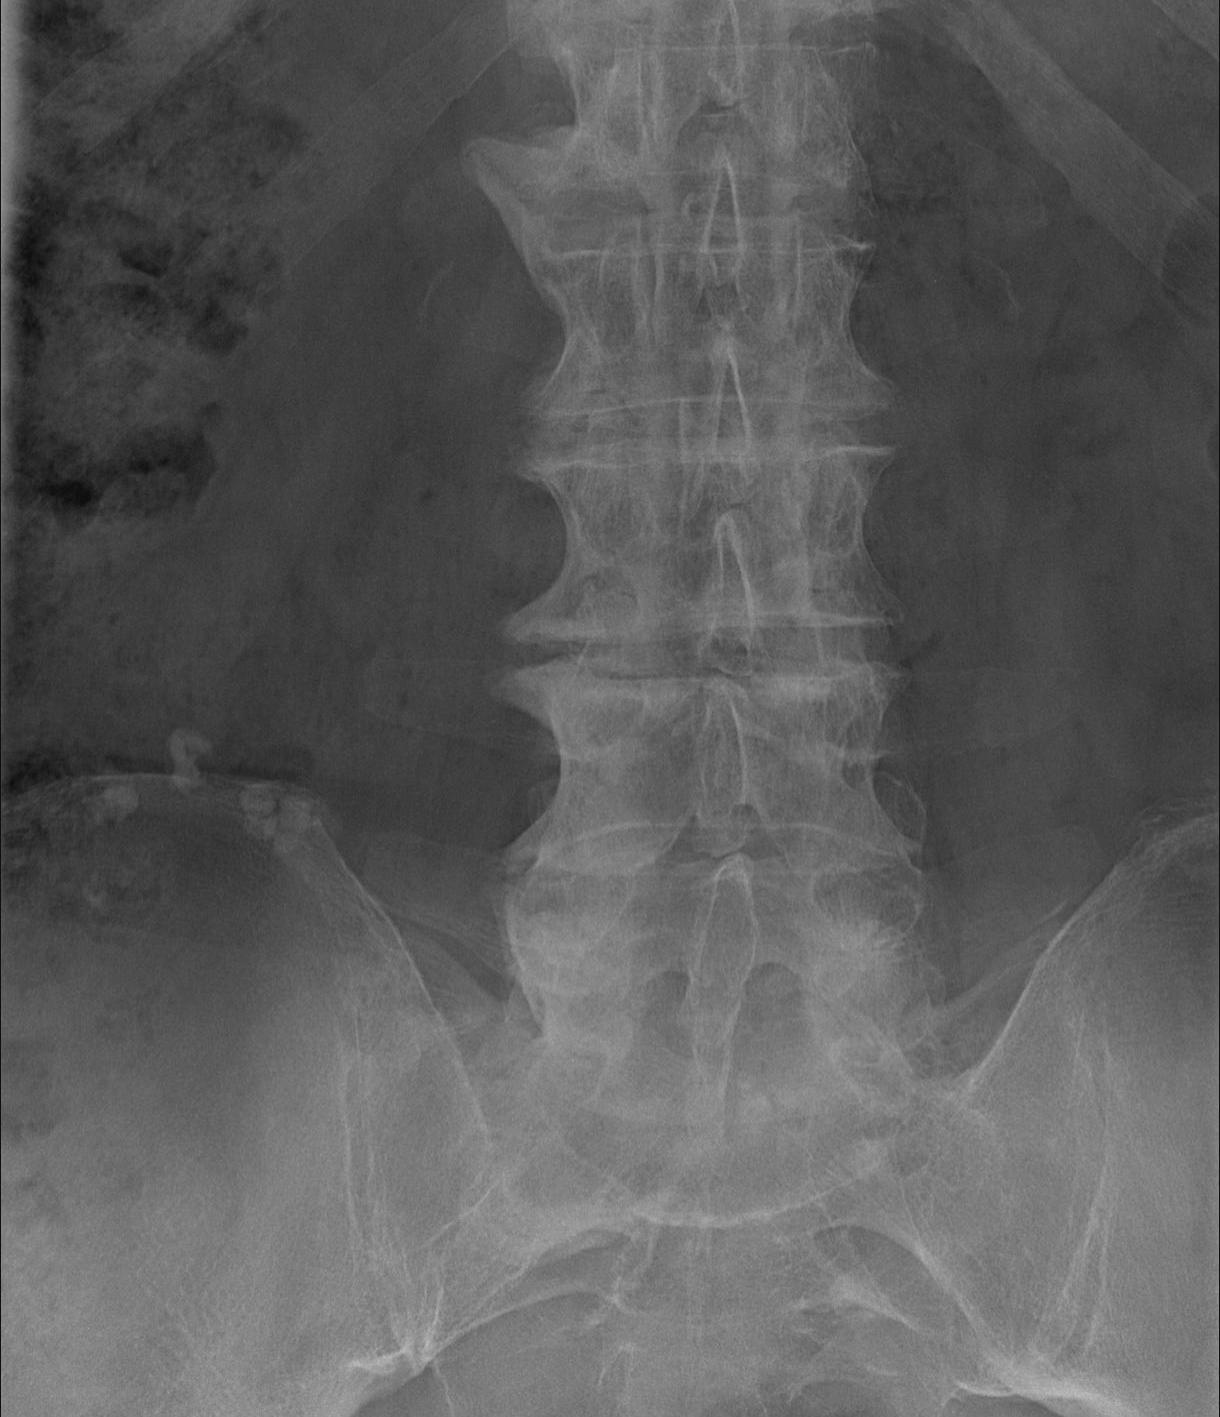

X-ray

Thoracic vertebra

Most common right sided and unilateral

- anterior & lateral spine

Non marginal syndesmophytes

- flowing / candle wax

Integrity of disc spaces & facet joints maintained

Lumbar spine

- least common

Pelvis

- osseous whiskering at sites of ligament attachment

- iliac crests / ischial tuberosity / trochanters